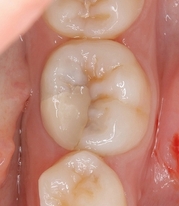

歯牙移植とヘミセクションから10年

先日昔治療させてもらった患者さんが詰め物が取れたということで来院されました。

この部位は

以前、延長ブリッジが入っていた歯

ふと、最近延長ブリッジ見なくなったなと思います。

特に問題無かった歯なので、このままにしておいたのですが、

5年後

遠心根に透過像が出てきており、歯茎からは膿が出てきていました。

日本の根管治療の約6割には問題があるというはあながち間違いではないと思います。

とりあえず根管治療をして治すことにしましたが、

近心根にはパフォーレーション 手付かずの遠心根には破折線が見られ、

患者さんにどうします!?遠心根はまず残せない、近心根は残すことが出来るがパフォーレーションの位置的に長く持たない可能性がある。

不思議なんですが、遠心根は根管治療していないにも関わらず折れてきている。

イメージ的に根管治療を行い中を削って歯を弱体化させている近心根が折れるならまだ分かるのですが・・・

患者さんと話し合い、近心根はヘミセクションをして残す 遠心根は抜歯

右下7の所には親知らずの移植と計画をしました。